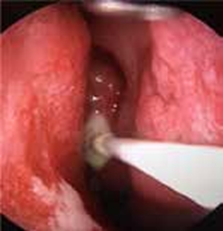

L’échographie abdominale réalisée objectivait une vésicule à paroi fine siège de plusieurs mini-calculs (Figures 1, 2).

Une cœlioscopie réalisée a montré de multiples granulations blanchâtres disséminées dans la totalité du foie, le reste de l’exploration était sans particularité (Figures 6 ,7). Une cholé-cystectomie associée à une biopsie hépatique objectivant une granulation blanchâtre, ont été réalisées.